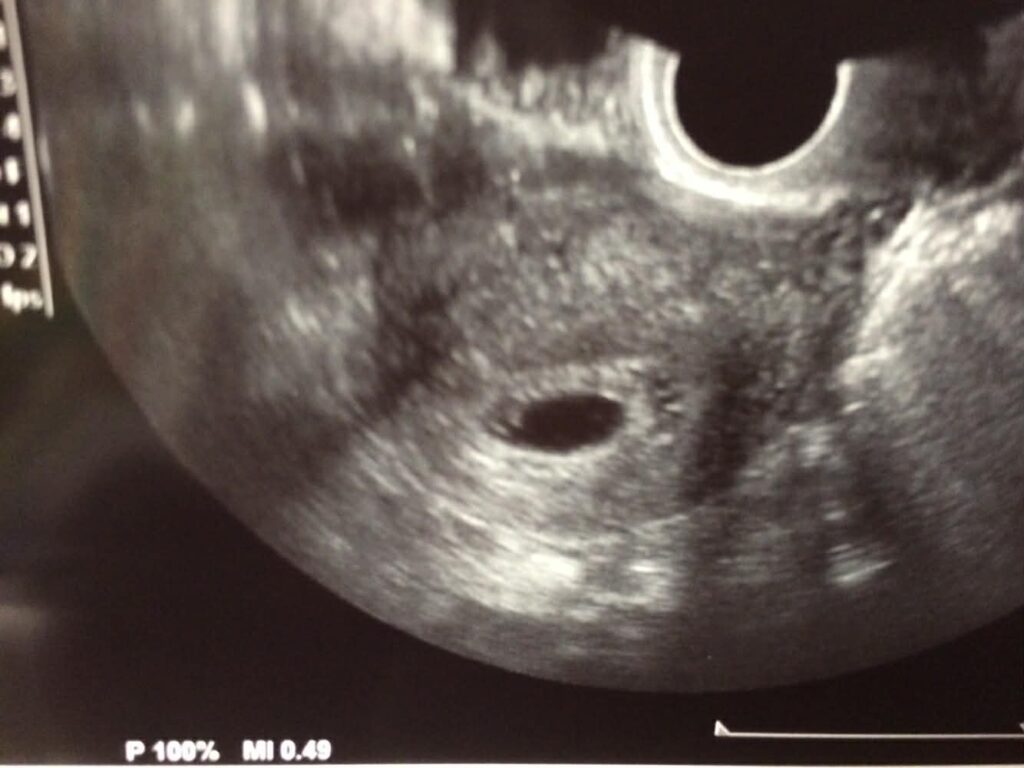

それに今回は、妊娠中に「妊娠性天疱瘡(にんしんせい てんぽうそう)」という、全身に強いかゆみと湿疹が出る皮膚の病気になってしまって。豆粒くらいの水ぶくれが体じゅうに出て、とにかくかゆくてかゆくて…2か月ほとんど眠れないような時期が続きました。いろいろ薬も使いましたが「根本的によくなるのは出産してから」と言われていて、実際、産んだ翌日にはピタッと症状が引いていったんです。